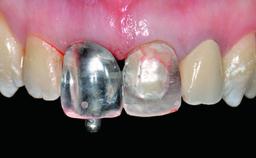

Replacement of an Ankylosed Central Incisor with a Gingival Recession: Tooth Extraction with Socket Grafting and Late Implant Placement with Simultaneous Contour Augmentation

Abutment Type CAD/CAM

Prosthesis Type FDP